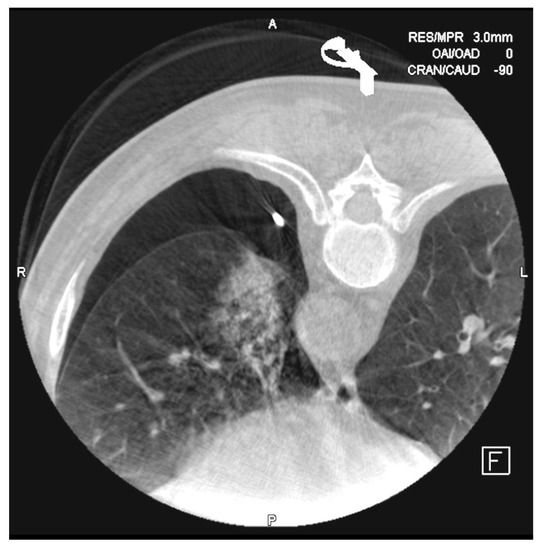

Cone-Beam CT-Guided Lung Biopsies: Results in 94 Patients

2. Materials and Methods